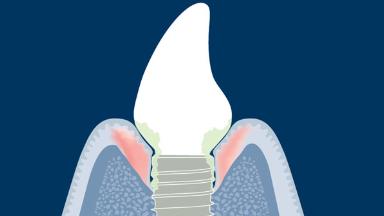

Complications that are associated with the surrounding peri-implant mucosa or bone are referred to as biological complications. They occur when there is an imbalance between the bacterial biofilm challenge to the tissues around an implant and the host defense, resulting in an inflammatory process.

The biological complications addressed in this module are the peri-implant diseases referred to as peri-implant mucositis and peri-implantitis, both of which may occur around osseointegrated implants.

Therefore, it is important that the clinician is able to diagnose peri-implant mucositis and peri-implantitis and understand the steps for management of these complications.